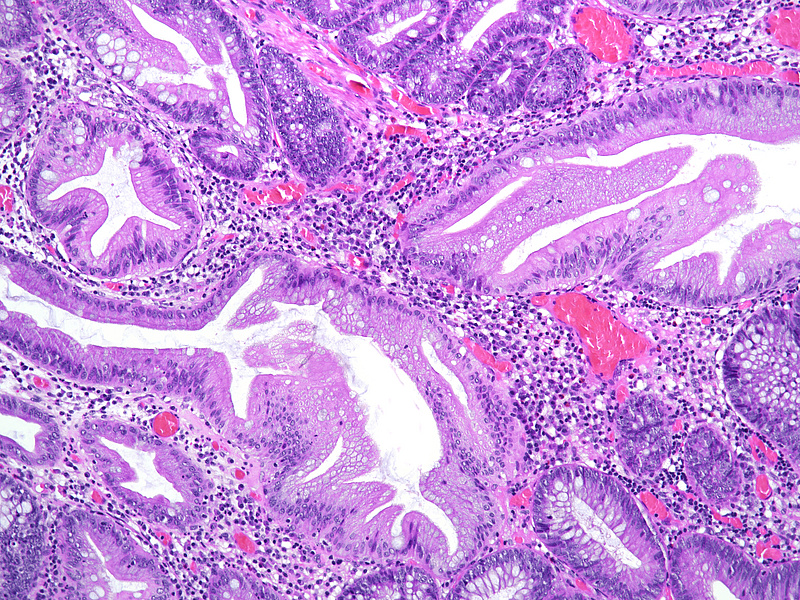

The ascending colon polyp is a serrated polyp characterized by a combination of two morphological patterns which are sessile serrated lesion (SSL) and traditional serrated adenoma (TSA). The former is formed by architecturally distorted serrated crypts with deep serrations, basal crypt dilatation and lateral growth along the muscularis mucosae (Panels A-B). Some foci of stromal proliferation resembling perineural cells are also seen within this component (Panel C). The TSA component has typical slit-like serrations, lined by tall columnar cells with intensely eosinophilic cytoplasm and pencillate nuclei (Panels D-E). Abrupt transition to dysplastic mucosa and glands are present, where the glands display more complex and crowded architecture with little intervening lamina propria (Panel F). The dysplastic cells show features of adenomatous dysplasia characterized by columnar cells with enlarged hyperchromatic nuclei, pseudostratification and reduced goblet cells (Panel G). In some areas, the cells display high grade cytology with more rounded nuclei and loss of polarity. MLH1 immunostaining was preserved in both the non-dysplastic and dysplastic glands with higher intense staining seen in the latter (Panel H).